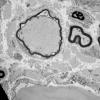

Giant Axonal Neuropathy (GAN) (2)